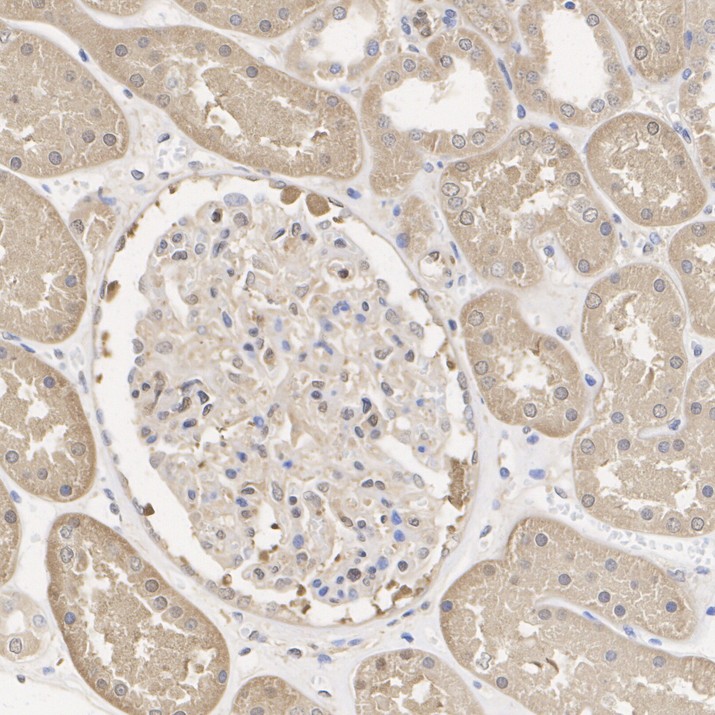

Immunohistochemical analysis of paraffin-embedded mouse kidney tissue with Rabbit anti-ATP citrate lyase antibody (ET1609-37) at 1/1,000 dilution.

The section was pre-treated using heat mediated antigen retrieval with Tris-EDTA buffer (pH 9.0) for 20 minutes. The tissues were blocked in 1% BSA for 20 minutes at room temperature, washed with ddH2O and PBS, and then probed with the primary antibody (ET1609-37) at 1/1,000 dilution for 1 hour at room temperature. The detection was performed using an HRP conjugated compact polymer system. DAB was used as the chromogen. Tissues were counterstained with hematoxylin and mounted with DPX.